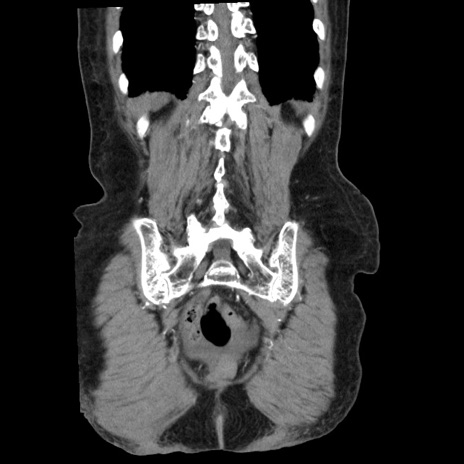

症例1(冠状断像)

症例

【症例】80歳代女性

【主訴】腹痛

【現病歴】8時間前から腹痛あり来院。

【既往歴】糖尿病、脂質異常症、子宮体癌にて子宮全摘術

【身体所見】意識清明・会話良好だが腹痛で苦悶様、全腹部にわたって反跳痛と圧痛あり

【データ】WBC 13600、CRP 0.14、LDH 224、CK 90

矢状断像